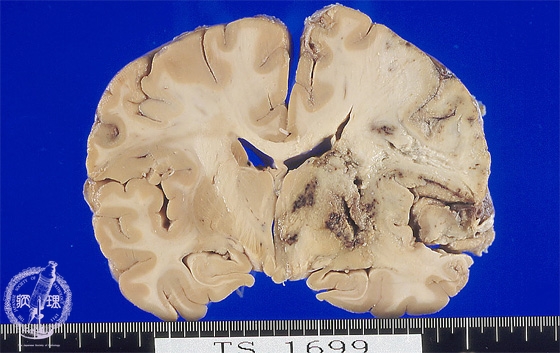

Macroscopic findings: Extensive infarction was detected from the right cerebral cortex to the basal ganglia. Infarcted region appeared pale and swollen and the cortex was indistinguishable from the medulla. Dark brown colored hemorrhage was also appreciated in the basal ganglia.

Click the image to see the enlarged image.